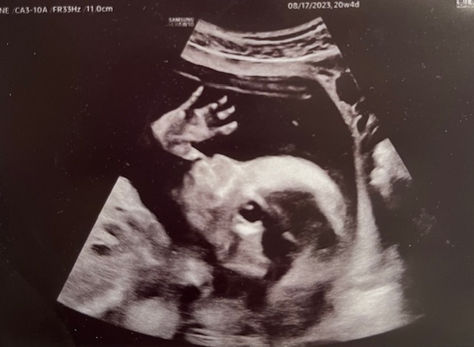

Congenital Heart Defect Awareness Week: Diagnosis Day

In honor of CHD (congenital heart defect) Awareness Week, we asked a Charlottesville heart warrior's family to share their story of...